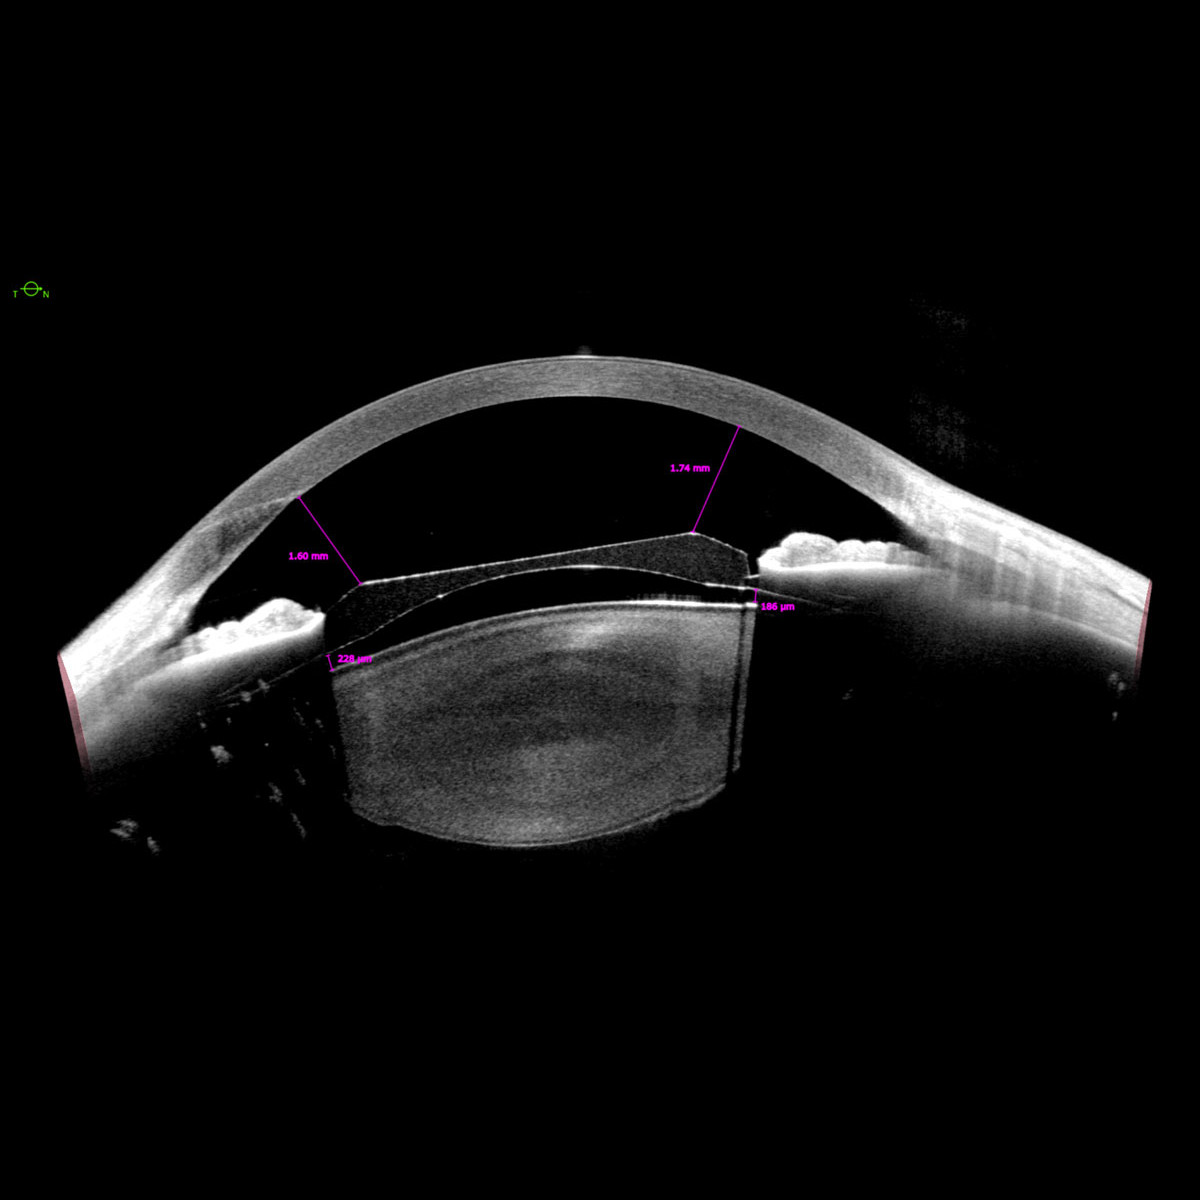

Als unverzichtbares Werkzeug für die Planung von Kataraktoperationen ermittelt ANTERION präzise biometrische Streckenmessungen sowie die gesamte Hornhautstärke, alles mit optimierter OCT-Technologie. So können Sie Ihre klinischen Ergebnisse selbst in den schwierigsten Fällen verbessern. Die OCT-Bilder helfen Ihnen dabei, Ihre Messungen zu bestätigen, sodass weniger Annahmen erforderlich sind.

Die Cataract App bietet sphärische und torische IOL-Berechnungen sowie Raytracing-Anwendungen und liefert die erforderlichen Daten zur Berechnung der für Ihre Patient:innen am besten geeigneten IOL, ohne dass Daten übertragen oder Geräte gewechselt werden müssen.